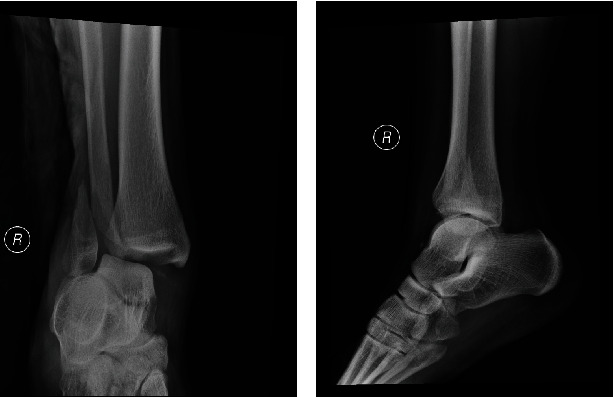

腓骨远端骨折是下肢常见的损伤。明显移位的腓骨远端骨折可在全身麻醉、脊髓麻醉或区域麻醉下进行手术固定治疗。我们介绍了一例腓骨远端移位骨折病例,区域麻醉和手术均由同一位骨科医生主治。患者成功接受了超声引导下的区域麻醉以及切开复位和内固定术。本病例报告重点介绍了超声引导下区域麻醉和外科医生手术固定的技术细节。

Distal fibula fracture is a common injury of the lower limb. Significantly displaced distal fibula fracture is treated with surgical fixation under general, spinal, or regional anesthesia. We present a case of displaced distal fibula fracture with both the regional anesthesia and operation performed by the same attending orthopedic surgeon. The patient underwent successful ultrasound-guided regional anesthesia as well as open reduction and internal fixation. This case report highlights the technical detail for ultrasound-guided regional anesthesia and surgical fixation by surgeon.